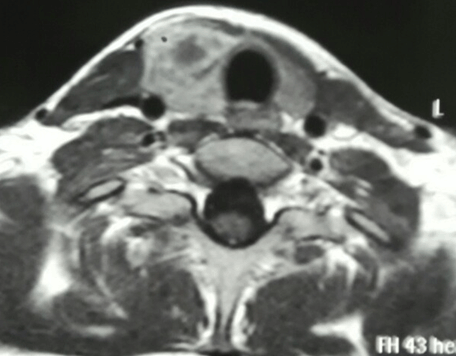

A 16-year-old girl presented with swelling in the right lobe of thyroid. There were no generalized symptoms like fever, malaise, night sweats and weight loss. There was no history of difficulty in deglutition or voice change. On clinical examination there was a single abscess of size 4x4 cm in right lobe of thyroid moving with deglutition. The margins were well demarcated, smooth surface, non-tender and overlying skin was normal with a tattoo mark on it (Figure 1). There were no clinical features of hypothyroidism or hyperthyroidism. Routine blood investigations were done; hemoglobin 11.0 g/dl, total leucocytes count 8600/mm3, neutrophils 67/mm3, lymphocytes 31/mm3 and eosinophils 2/mm3. The erythrocyte sedimentation rate was 20 mm. The Mountax test was highly positive more than 10 mm in diameter. Thyroid function tests T3, T4, TSH were normal. X-ray chest was normal. Ultrasonography of neck revealed a 50x45x20 mm solitary nodule in the right lobe of liver. This solitary thyroid nodule was showing thick irregular wall with central necrosis reported as suspected thyroid abscess. Magnetic resonance imaging scan of the neck showed a lesion of intermediate signal intensity due to presence of dense inflammatory cells and granulomas with central necrosis (Figure 2). A doubt about carcinoma of thyroid was placed as differential diagnosis. The CECT scan of neck was done to rule out carcinoma of thyroid gland. This was helpful in diagnosis of tubercular thyroid abscess as localized caseous lesion in right lobe of thyroid (Figure 3). Fine needle aspiration from this solitary thyroid nodule was done to confirm the diagnosis. The stained smears revealed degenerated and intact neutrophils, and macrophages in serofibrinous background. A few epithelioid granuloma and multinucleated giant cells are also seen suggestive of tuberculosis with central caseous necrosis. Ziehl–Neelsen staining with 20% H2SO4 was noncontributory (Figure 4). From the central part of swelling about 2 ml of thick yellow color pus was aspirated as shown in Figure 5. The smears prepared from this pus did not show any acid-fast bacilli. After aspiration the swelling decreased in size. The cytological diagnosis of tubercular abscess was made. The patient was put on antitubercular treatment with four drug regimens. The swelling decreased in size in next three months (Figure 6). She was asked to continue on three drug regimens for another six months leading to complete resolution of swelling. | ||||||